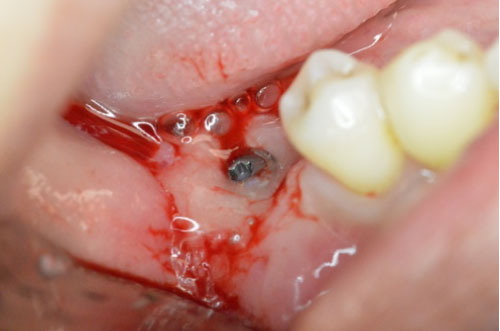

A 41-years-old patient presented with a restored dental implant in the mandibular posterior molar area, the implant fixture was placed approximately eight years ago and restored few months afterwards. The intra-oral exam revealed 5-6 mm pockets around the implant with slight inflammation of the surrounding soft tissue including bleeding upon probing and exudate. No mobility was detected and the patient was asymptomatic. The radiographic exam (Figure 1) revealed considerable bone loss with no other findings. The implant crown was removed and a cover screw placed. The Surgical treatment included a circumferential incision around the implant (Figure 2) followed by excavating the granulation tissue into the bony defect, scaling the implant surface using ultrasonic scalers and then using Prefgel to decontaminate the implant surface (Figure 3). A bone mix of mineralized cortico-cancellous allograft with Amnion-Chorion strips used to fill the bone defect (Figure 4 and Figure 5) and followed by mono filament non-resorbable suture (Figure 6). The patient placed on systemic antibiotics for one week and was prescribed chlorhexidine mouth wash in addition to mild analgesics. Two weeks post-operatively the patient presented with uneventful healing of the soft tissue and complete healing of the surgical wound over the bone graft mass (Figure 7). Three months following the procedure a periapical film showed considerable fill of the bone defect with integration to the implant surface (Figure 8).

Figure 3: Prefgel placed around the implant following ultrasonic debridement. View Figure 3